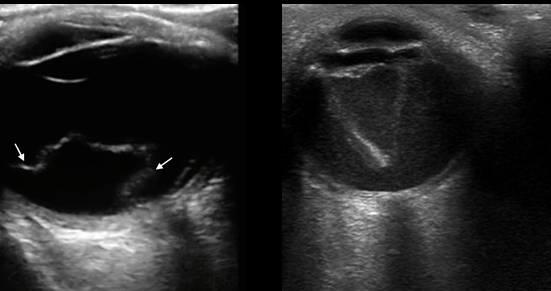

US en desprendimiento retina

Retina doblada y brillante (gusanito)

Forma triangular